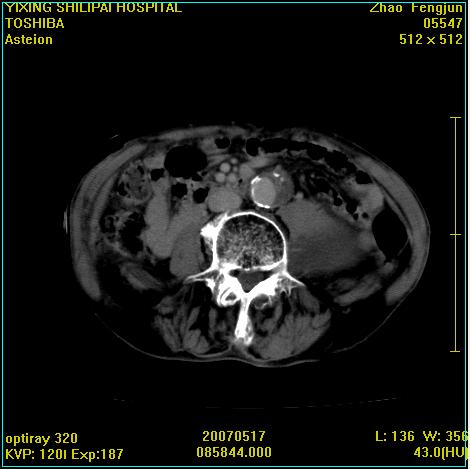

考虑:1、左侧腰大肌囊实性占位性病变(囊性神经根鞘瘤?);

2、右侧兰尾区囊性占位性病变(兰尾囊肿?囊腺癌?类癌?)

以下是引用xiaoniu在2007-5-26 10:45:00的发言:[br]腰大肌的病变应该没有问题,增强扫描还有轻度强化及细小血管影入内,应该排除脓肿,考虑占位性病变,腰大肌的占位多考虑:神经源性肿瘤。另外腹主动脉下端有真假腔的强化,考虑:主动脉夹层。[br][br][本贴已被 xiaoniu 于 2007-5-26 10:46:39 修改过]

以下是引用老爱克斯新网客在2007-5-26 18:26:00的发言:[br]1左下腹囊实性占位肿块,增强后不均匀强化,位于脊柱旁,椎体骨质无破坏软组织无肿胀,考虑神经源肿瘤神经鞘瘤可能大,2右下腹囊性占位性病变,增强后囊壁强化,考虑阑尾囊肿或囊腺瘤,